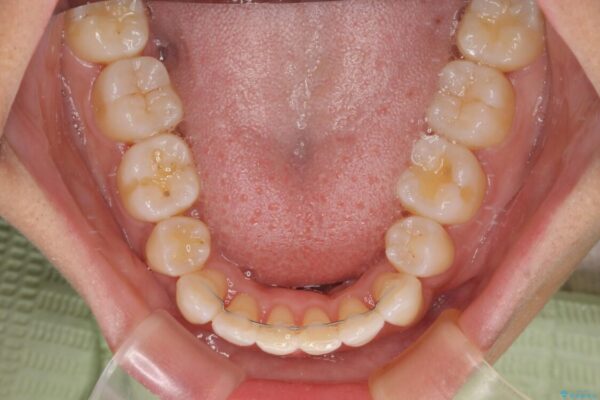

治療後

• 抜歯矯正で唇を閉じやすく 目立たないワイヤー装置 治療後画像